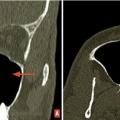

Polypose nasosinusienne

La polypose nasosinusienne est une rhinosinusite diffuse caractérisée par la présence de polypes bilatéraux dans les cavités nasales venant du massif ethmoïdal. Sa physiopathologie repose sur une inflammation chronique de la muqueuse des cavités nasales et sinusiennes marquée par une infiltration éosinophilique plus ou moins…

Tableaux et figures